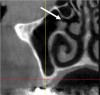

Submandibular Fossa and Mylohyoid Ridge

The submandibular fossa is denoted by an undercut in the posterior mandible (Figure 3). It is located beneath the mylohyoid muscle. This site must be intraorally palpated before implant placement because there may be an undercut in the mandibular molar area. In this regard, Parnia et al reported that 52% of patients manifest concavities 2 mm to 3 mm deep, and 28% of the examined regions demonstrated concavities of more than 3 mm.11 Thus, when there is a large undercut, caution must be exercised in order to avoid drilling into the floor of the mouth, which could sever a blood vessel and result in hemorrhaging. The ridge on the lingual aspect of the mandible depicted in Figure 3 is the mylohyoid ridge, which provides the origin of the mylohyoid muscle.